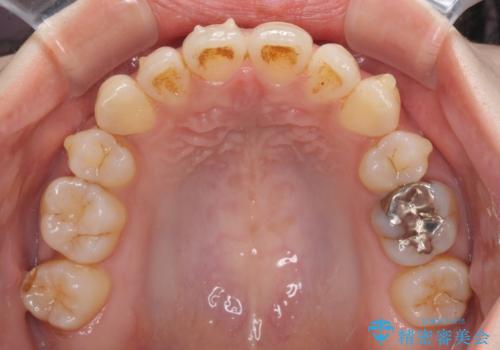

軽度な歯列不正 インビザライン・ライトによる矯正治療

- 上下前歯の叢生を気にして来院された患者様です。

費用を抑え、期間もあまりかけずに治療をしたいとのことで、インビザライン・ライトを用いて矯正治療を行うこととしました。

インビザライン・ライトは、製作できるアライナーの枚数に制限があるため、移動可能な量に限りがあります。

一方で、半年程度で治療を終えることができるため、軽度の歯列不正の患者様には大変お勧めです。